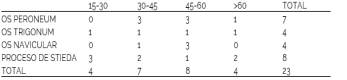

El rango de edad en los 23 pacientes con hallazgo de huesos accesorios tarsianos estuvo entre 15 y 85 años, con distribución homogénea de variantes por franja etárea. (Tabla 3).